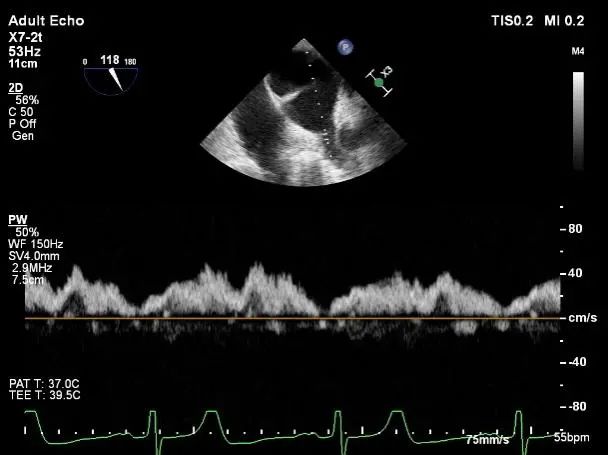

术后肺静脉频谱

二尖瓣瓣口面积及平均跨瓣压差评估(5mmHg)